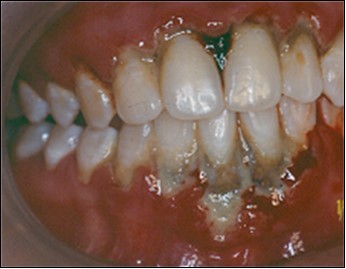

A partial thickness flap is created with two vertical incisions placed at least one-half to one tooth wider mesiodistally than the area of gingival recession. The coronal margin of the flap is started with a horizontal sulcular incision to preserve all existing radicular gingiva. The interproximal papillae are left intact. The flap dissection is partial thickness leaving connective tissue over the existing bone and / or root surfaces. The root of the involved tooth is carefully scaled and planed until its surface is smooth and hard. Er-YAG laser is then applied to its surface to promote root biomodification, at powers ranging from 25 to 50 mJ/pulse/sec. (Figure 3, Figure 3A).

Figure 3A.Er-Yag laser being applied to promote root biomodification